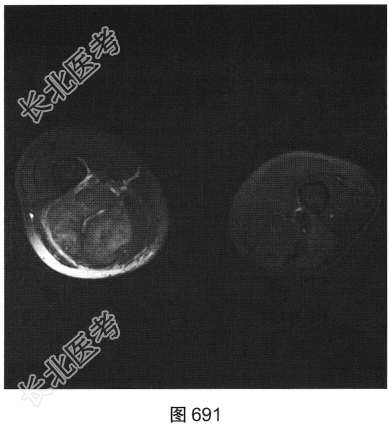

- 多项选择题3.[提示]为进一步明确诊断,患者进一步行CT及MRI检查, 如图686~图691所示。患者CT及MRI的阳性影像表现有( )

A、T2压脂序列上肿块内可见条状高信号

B、右大腿后方肌群内见肿块影

C、T1WI及T2WI均表现为实性肿块,均以等信号为主

D、T2压脂序列呈高信号,周围见明显水肿信号

E、肿块边界较清,密度较均匀

F、肿块周围肌间隙清晰,邻近组织呈受压改变

G、T2WI上可见斑片状稍高信号及低信号分隔

关注下方微信公众号,搜题查看答案